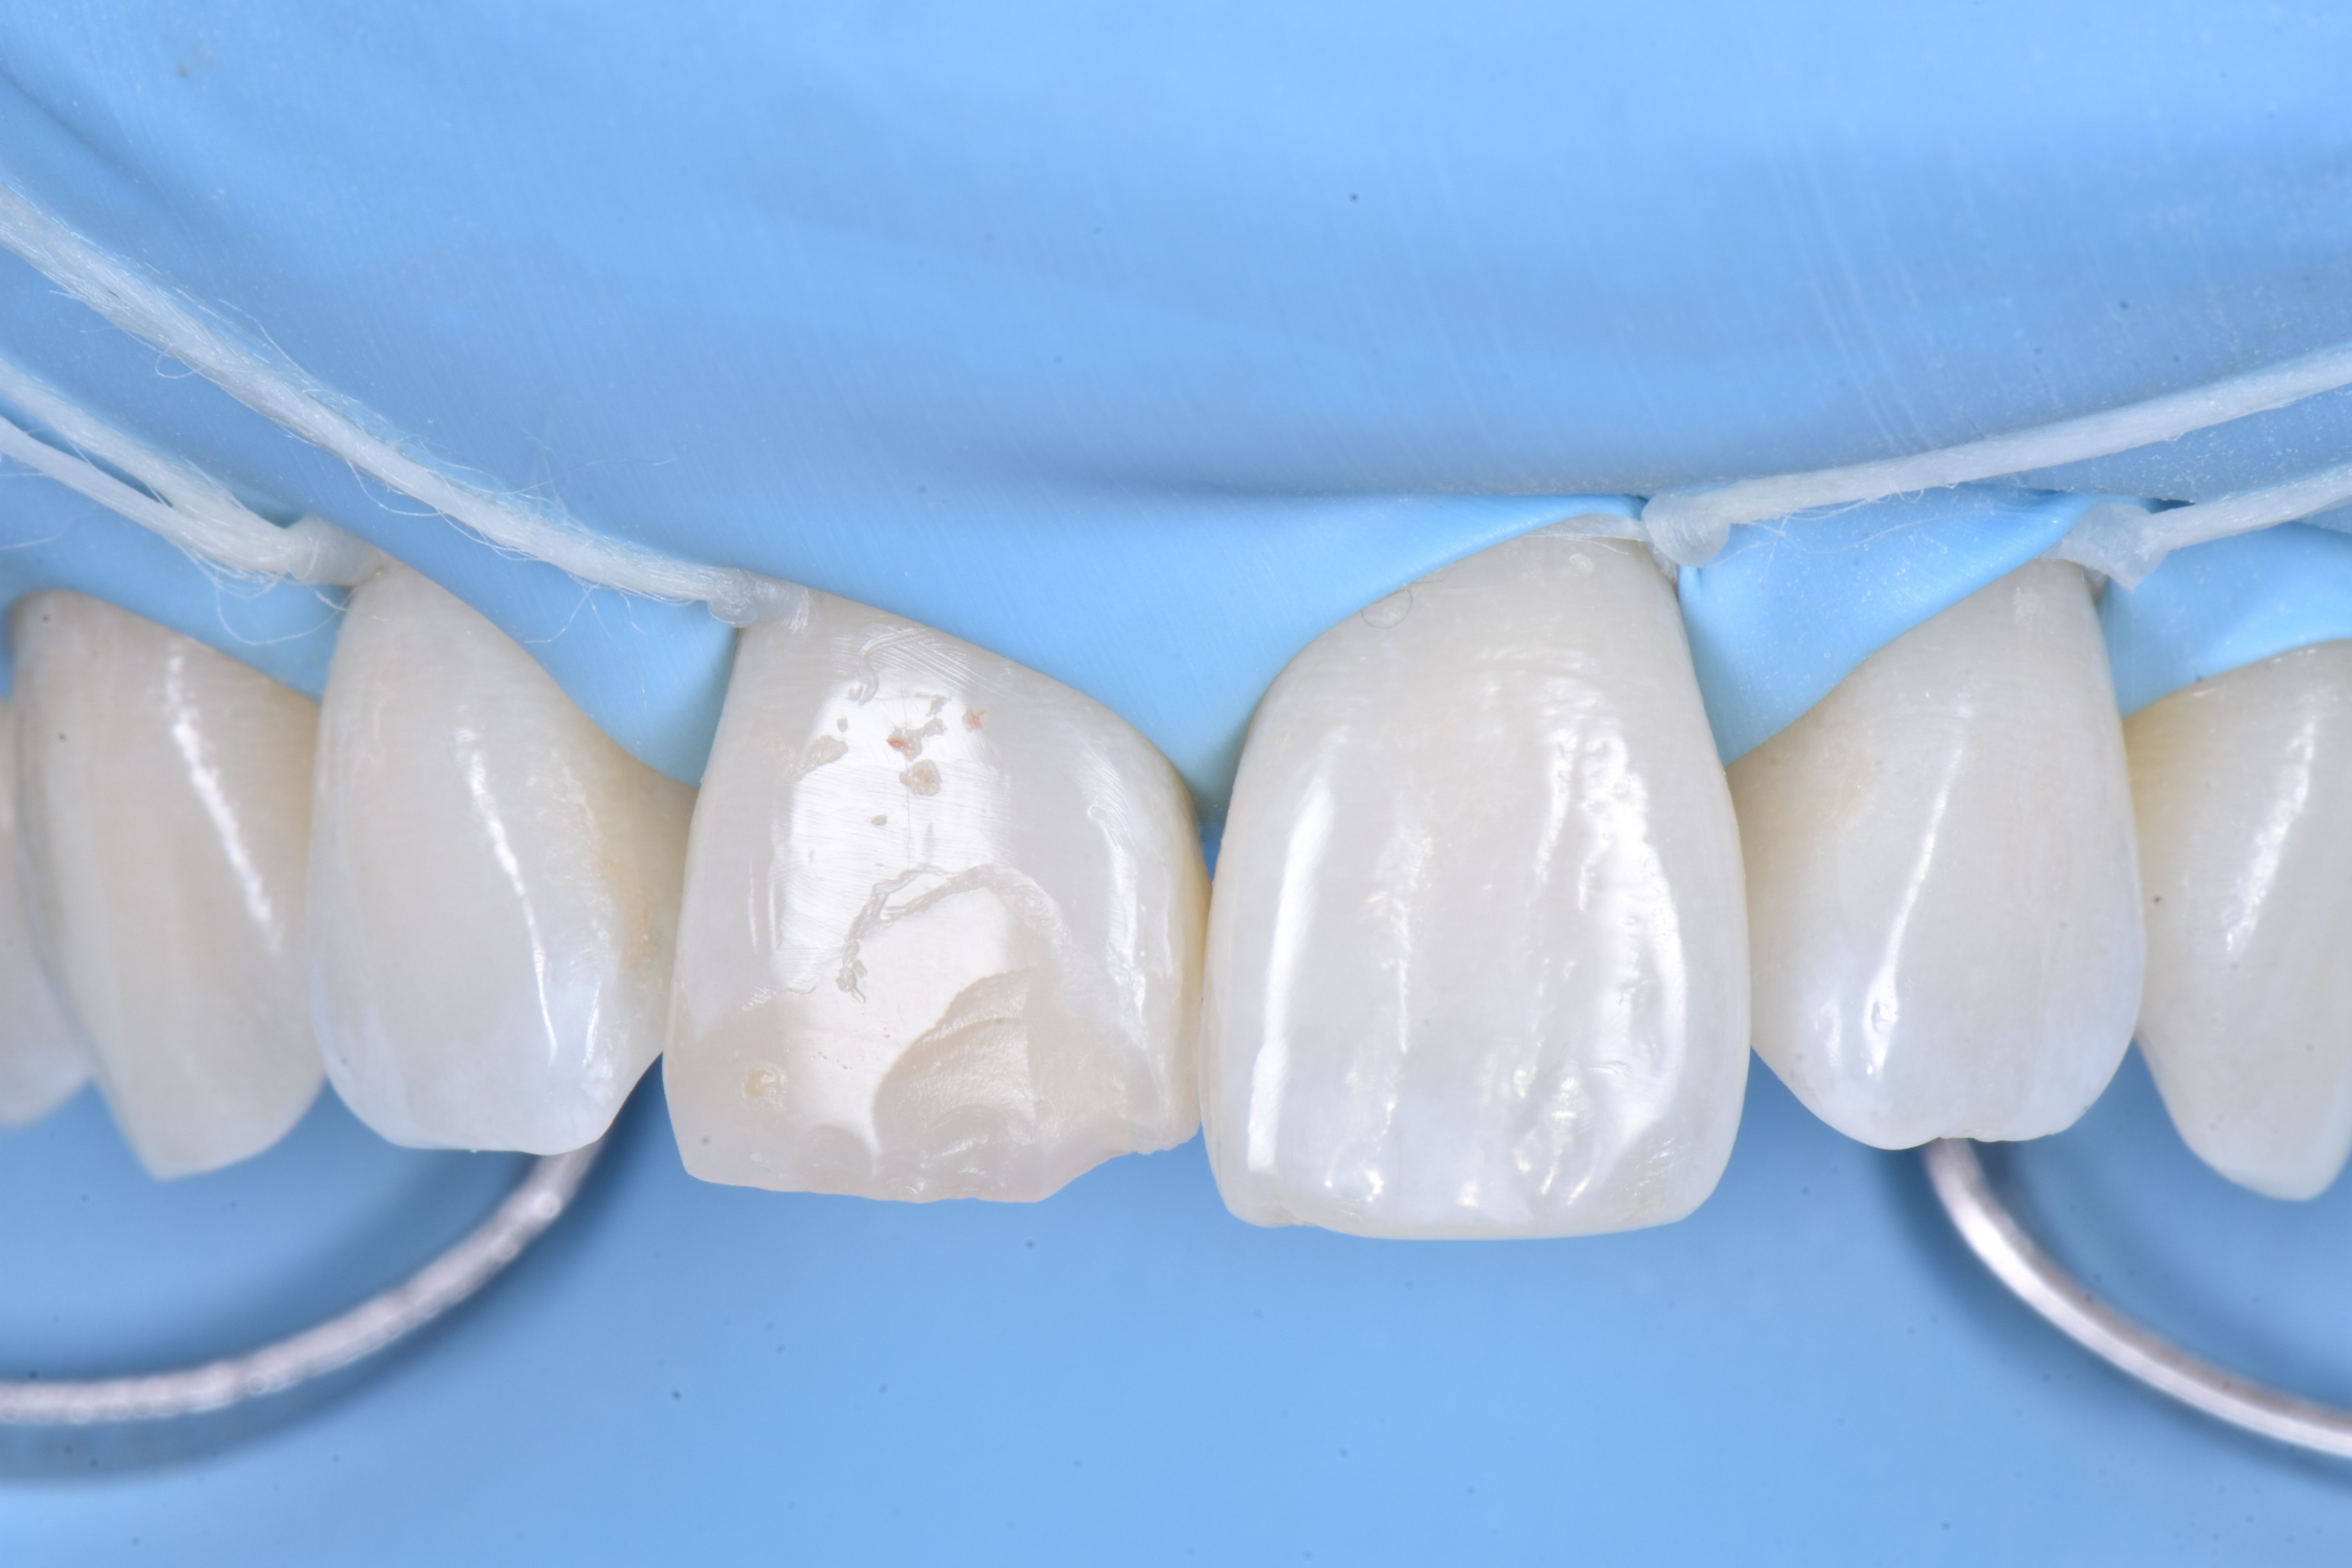

W dniu zabiegu, po wykonaniu miejscowego znieczulenia, ząb 11 odizolowano za pomocą koferdamu, rozszerzając izolację na pierwsze zęby przedtrzonowe (ryc. 4).

Następnie usunięto pękniętą rekonstrukcję kompozytową i wykonano niewielkie zukośnienie, a całą powierzchnię zęba 11 wypiaskowano tlenkiem glinu w proszku 27 μm (ryc. 5).